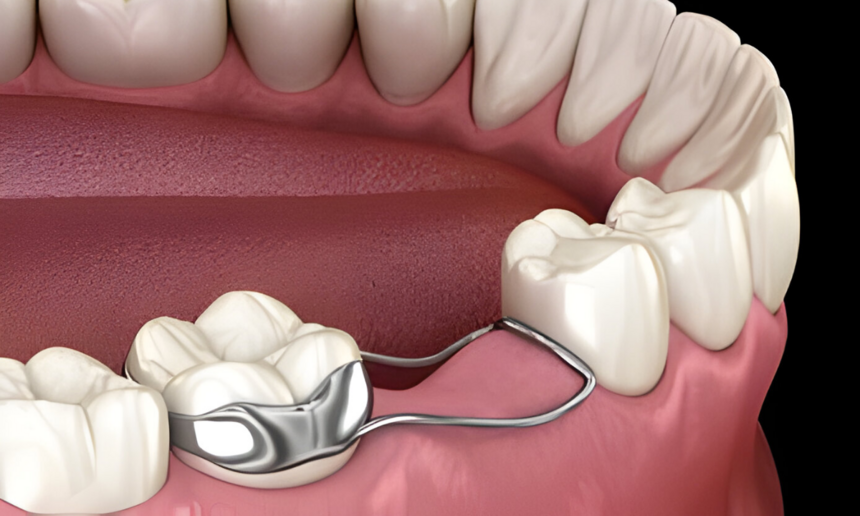

Space Maintainer

A child’s dental health plays a crucial role in their overall well-being. When a primary tooth is lost too soon, it can lead to serious alignment issues in the future. This is where a space maintainer...